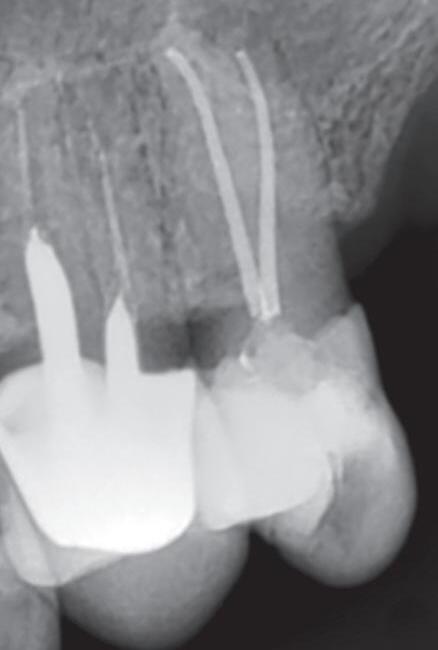

Fig. 19-1. Paciente idoso submetido a tratamento endodôntico (dente 25). (a) Canais atresiados (visualizados na radiografia periapical.) ( bliteração da entrada do canal vestibular. (d) Canal localizado e ampliado (uso de microscopia e ultrassom). ( a